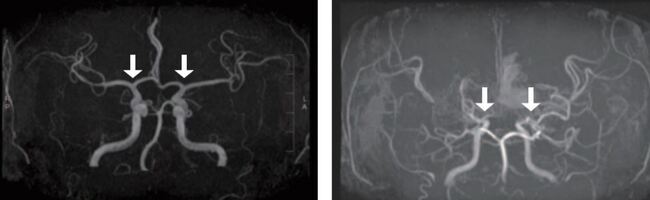

김승기 교수는 “이번 연구는 혈액검사를 통해 모야모야병의 조기진단이 가능하다는 것을 입증했다”며 “모야모야병의 조기진단과 맞춤형치료를 위한 중요한 첫걸음을 내딛은 것으로, 소아 환자들이 비침습적인 진단 및 치료에 기여할 것”이라고 전망했다.    정상(왼쪽) 및 모야모야병 환자의 뇌혈관모야모야병은 특별한 원인 없이 대뇌에 혈액을 공급하는 내경동맥의 가지 치는 부위 혈관이 서서히 좁아지는 만성 진행성 뇌혈관질환이다. 이로 인해 혈류가 부족해지고, 부족한 혈류를 보충하려 비정상적인 미세혈관들이 자라나지만, 이 혈관들은 혈액을 충분히 공급하지 못하고 터지기 쉬워 뇌경색이나 뇌출혈과 같은 심각한 소아 뇌졸중을 유발하게 된다.

지금까지 모야모야병을 확진하기 위해서는 침습적인 뇌혈관조영술이 표준검사였고, 이는 소아에게 큰 부담을 주었다. 자기공명영상 및 자기공명혈관조영술(MRI/MRA)와 같은 비침습적 검사도 있지만, 혈관 협착이 과장되게 나타나는 경우가 있고 뇌기저부의 모야모야혈관을 자세히 평가하기 어려워 한계가 있었다. 이에 따라 혈액 기반의 액체생검 필요성이 꾸준히 제기되어 왔다.